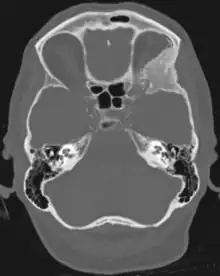

Sphenoid wing meningiomas are diagnosed by the combination of suggestive symptoms from the history and physical and neuroimaging by magnetic resonance imaging (MRI) or computer averaged tomography (CT). Tumors growing in the inner wing (clinoidal) most often cause direct damage to the optic nerve leading especially to a decrease in visual acuity, progressive loss of color vision, defects in the field of vision (especially cecocentral), and an afferent pupillary defect. If the tumor continues to grow and push on the optic nerve, all vision will be lost in that eye as the nerve atrophies. Proptosis, or anterior displacement of the eye, and palpebral swelling may also occur when the tumor impinges on the cavernous sinus by blocking venous return and leading to congestion. Damage to cranial nerves in the cavernous sinus leads to diplopia. Cranial nerve VI is often the first affected, leading to diplopia with lateral gaze. If cranial nerve V-1 is damaged, the patient will have pain and altered sensation over the front and top of the head. Horner's syndrome may occur if nearby sympathetic fibers are involved.

Tumors found in the external third of the sphenoid are of two types: en-plaque and globoid meningiomas. En plaque meningiomas characteristically lead to slowly increasing proptosis with the eye angled downward. Much of this is due to reactive orbital hyperostosis. With invasion of the tumor into the orbit, diplopia is common. Patients with globoid meningiomas often present only with signs of increased intracranial pressure. This leads to various other symptoms including headache and a swollen optic disc. The differential diagnosis for sphenoid wing meningioma includes other types of tumors such as optic nerve sheath meningioma, cranial osteosarcoma, metastases, and also sarcoidosis. Following the physical exam, the diagnosis is confirmed with neuro-imaging. Either a head CT or MRI with contrast such as gadolinium is useful, as meningiomas often show homogenous enhancement. Angiography looking for signs like stretched arteries may be used to supplement evaluation of vascular involvement and to determine whether embolization would be helpful if surgery is being considered.